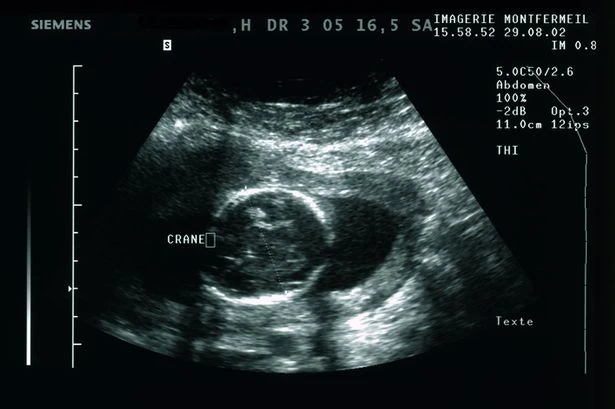

Nghiên cứu này có thể sẽ là bước tiến mang tính lịch sử của y học hiện đại. Ảnh: Mirror